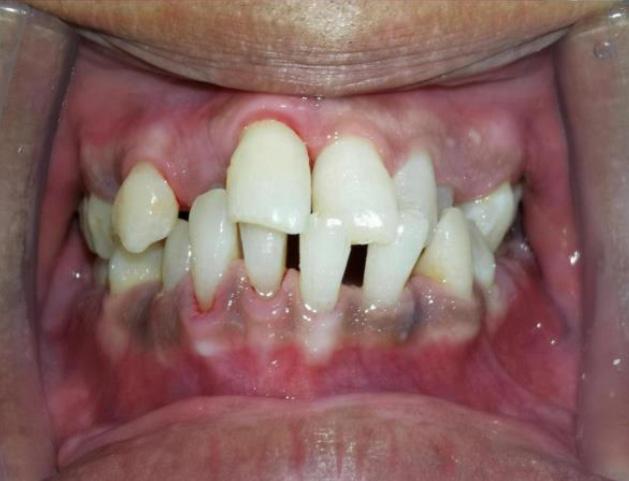

Apakah yang terjadi selepas rawatan penskaleran ini?

Anda akan merasa mulut dan gigi lebih bersih dan licin berbanding sebelum rawatan. Terdapat beberapa pesakit menyatakan mereka merasa lubang atau ruang di celah-celah gigi yang sebelum ini tidak pernah wujud akan terasa di ruang tersebut. Untuk pengetahuan umum, Tuhan telah menciptakan sesuatu sebaikbaik kejadian termasuklah ruang di antara gigi bagi memudahkan aliran air liur dan makanan. Air liur bukan sahaja bertugas sebagai ‘pelincir’ apabila kita makan, tetapi juga mempunyai sifat anti bakteria yang boleh mencuci dan membunuh kuman bahaya dalam mulut.

Oleh kerana makanan sering berada di celah-celah atau ruang di antara gigi, lama kelamaan makanan tersebut menjadi tartar dan tidak dapat dicuci menggunakan berus gigi biasa. Maka dengan itu, lama-kelamaan ruang tersebut tertutup dan anda akan merasakan tiada ruang dicelah permukaan gigi. Setelah rawatan penskaleran ini dilakukan, kesihatan gusi anda akan menjadi lebih baik dan anda akan merasakan tanda-tanda penyakit gusi seperti gusi mudah berdarah sewaktu memberus gigi akan berkurangan.

Sebelum rawatan penskaleran Selepas rawatan penskaleran Keadaan gigi yang tidak pernah melakukan rawatan penskaleran. (A) menunjukkan tartar yang berkumpul pada gusi (B) gusi berwarna merah, bengkak dan lembut seperti span (C) gigi kelihatan lebih panjang dan bergoyang akibat penurunan gusi dan tulangLUMUT, 10 Oktober 2023 - Sambutan Hari